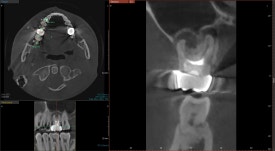

20240805

CT를 찍어보니 오른쪽 위 신경치료한 치아에서

염증이 발생한 것을 알 수 있었습니다.

치아 내부에 원인이 있는 경우,

염증은 대개 뿌리 끝에 동그랗게 잡히게 됩니다.

CT를 면밀히 분석한 결과,

이전에 받은 신경치료에서

놓친 부위가 있다는 것을

확인할 수 있었습니다.